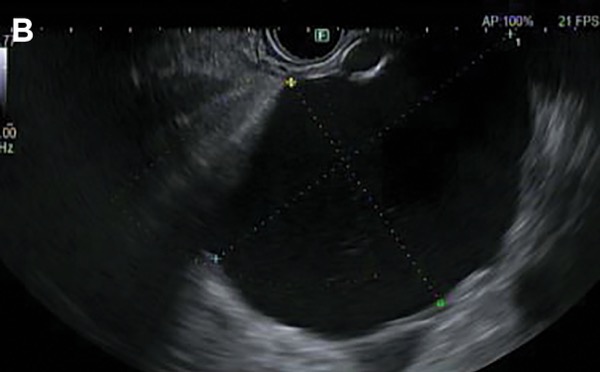

A 67-year-old man presents to the emergency department with a 3-week history of progressive post-prandial fullness, early satiety and nausea. He has a history of chronic alcohol use and multiple prior admissions for alcohol-related pancreatitis. CT scan reveals a 7- × 8-cm cystic lesion arising from the body of the pancreas, as well as extensive pancreatic calcifications consistent with chronic pancreatitis (Figure 1A). EUS with FNA reveals thin, brown fluid with an amylase level of greater than 15,000 U/L and a CEA of less than 5 ng/mL (Figure 1B). The patient is diagnosed with a pancreatic pseudocyst. An EUS-guided cystogastrostomy is performed, with complete resolution of the patient’s symptoms.

Pseudocysts occur in the setting of pancreatitis. Clues on history include a discrete episode of pancreatitis (acute epigastric pain associated with nausea and vomiting, lipase or amylase 3 times the upper limit of normal, and imaging evidence of pancreatitis) and risk factors of pancreatitis (heavy alcohol use, gallstones, hypertriglyceridemia). Pseudocysts occur more than 4 weeks after the onset of interstitial pancreatitis. On imaging, they appear as an encapsulated unilocular collection of fluid with a well-defined inflammatory wall usually outside the pancreas, with minimal or no necrosis. Communication with the pancreatic duct usually is demonstrated. Although pseudocysts have no malignant potential, pancreatic cancer sometimes can present as acute pancreatitis, and a pseudocyst may develop in that setting. Given this, EUS is recommended for patients over 40 years of age with acute pancreatitis without a clear cause.8 In cases of diagnostic uncertainty, EUS-FNA is useful. Fluid from pseudocysts is dark yellow or brown and has an elevated amylase level (>250 U/L) and a low CEA level (<5 ng/mL). Pseudocysts do not require surveillance but require drainage if they are symptomatic.